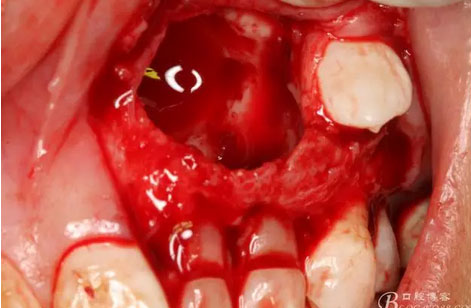

圖18.摘除囊腫后遺留的巨大骨腔

圖19.生理鹽水沖洗骨腔,修整骨腔表面

圖22.為了保留兩顆乳牙,不再去除遺留部分鈣化物,遂膠原蛋白海綿填塞兩個(gè)缺損骨腔。